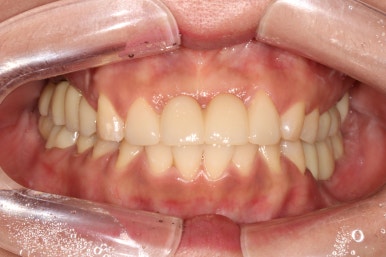

Before & After

좌측이 치료 전, 우측이 치료 후 정면 사진입니다.

솔직히 이제 치료를 받은 곳이 있으신가? 싶을 정도로 깔끔하게 마무리가 잘 된 것 같아요.

예쁜 앞니 지르코니아 크라운 제작은 저희 치과의 자랑입니다! 정말 색깔 잘 나왔네요~